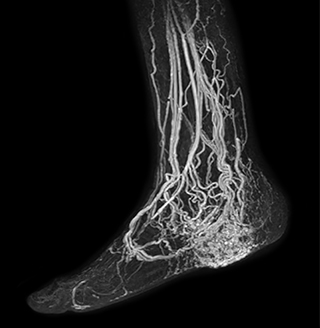

MRA run-off study with mDIXON

The subtractionless peripheral MR angiography shows improved vessel-to-background contrast and high resolution. Ingenia Ambition 1.5T.

Station

Ingenia Ambition

Pelvis

Voxels 1.3 x 1.3 x 3.2 mm, FOV 430 mm, 125 slices

Upper legs

Lower legs

Voxels 1.0 x 0.82 x 2.0 mm, FOV 430 mm, 125 slices